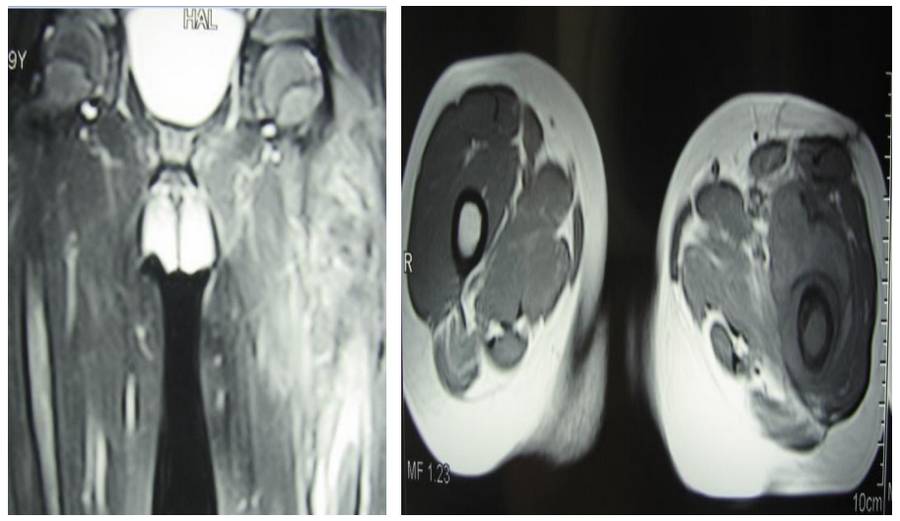

Ameliyat Öncesi: MR’da çevreleyen yumuşak doku kitlesi ve ödem görülmekte